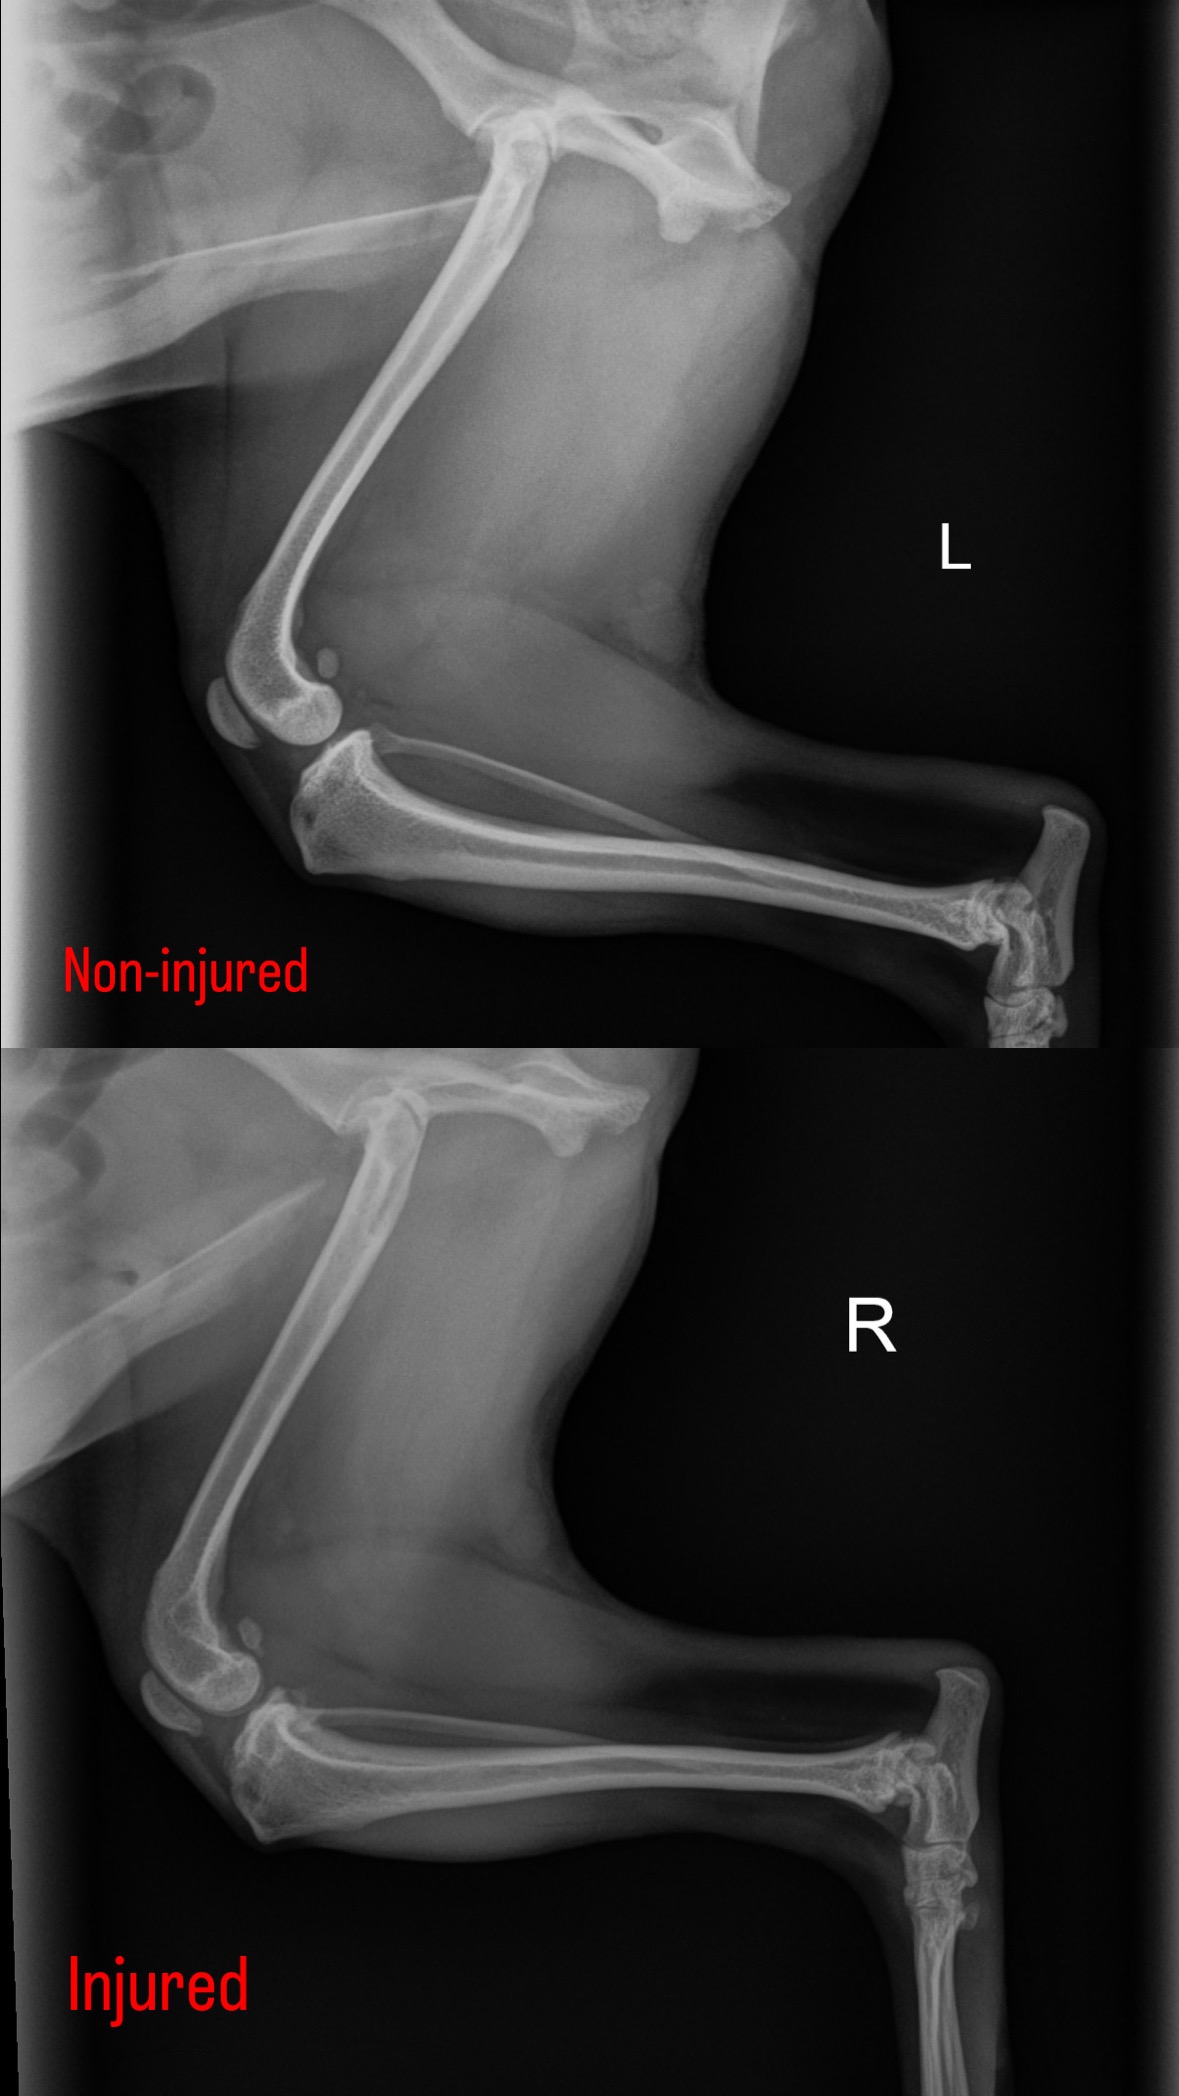

My dog Teddy has a torn cruciate ligament in his right back leg and needs surgery to walk without pain. Right now, he's limping, uncomfortable, and starting to show early signs of arthritis—even though he's only 5 years old. It's hard to watch him struggle with something that can be treated, but the cost of surgery is more than I can afford on my own.